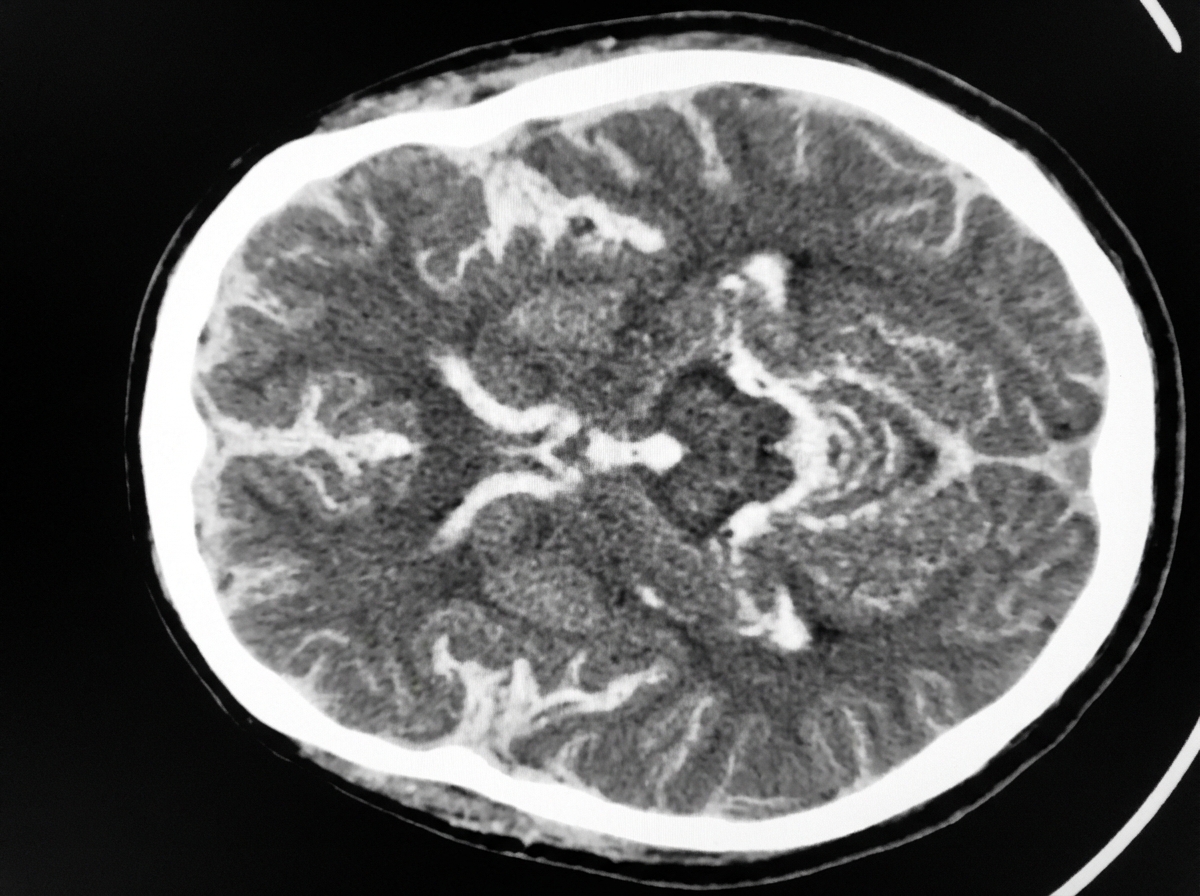

Intracranial Hemorrhage - Brain Bleed Breakdown

- CT: Biconvex (lentiform) hematoma. Does not cross suture lines.

- CT: Crescent-shaped hematoma. Can cross suture lines.

- Epidural hematoma: Middle meningeal artery rupture, classic lucid interval, and lentiform (biconvex) CT shape; does not cross suture lines.

- Subdural hematoma: Tearing of bridging veins, crescent-shaped hematoma on CT that crosses suture lines; common in elderly and alcoholics.